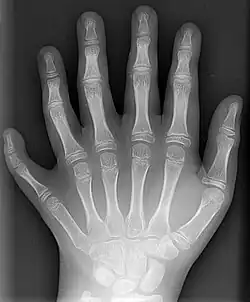

Já no punho, existem oito ossos, referidos conjuntamente como ossos carpais. Tais ossos se organizam em duas fileiras: a fileira proximal (constituída, de lateral para medial, pelos ossos escafoide, semilunar, piramidal e pisiforme); e a fileira distal (formada, também de lateral para medial, por trapézio, trapezoide, capitato e hamato). Trata-se de ossos curtos, que conferem grande flexibilidade ao punho. A fileira proximal dos ossos carpais se articula, em primeiro lugar, com o rádio. Além disso, uma fileira de ossos carpais estabelece articulação com a outra. Por fim, existe articulação entre a fileira distal dos ossos carpais e os ossos metacarapais.[3]

Na sequência, há os ossos que constituem a palma da mão, chamados de ossos metacarpais, numerados de um a cinco.[3] O primeiro osso metacarpal é aquele que se articula com a falange proximal do primeiro dedo (polegar), ao passo que o quinto osso metacarpal é o que estabelece articulação com a falange distal do quinto dedo (mínimo).[8] Apesar do pequeno tamanho, os ossos metacarpais são classificados como ossos longos devido a sua estrutura. Além disso, estabelecem articulação com ossos carpais e falanges proximais.[9]

Enfim, os ossos encontrados nos dedos recebem a nomenclatura de falanges. Em geral, os dedos possuem três falanges: falange proximal (mais próxima da palma da mão), falange média (intermediária) e falange distal (mais distante da palma da mão). No entanto, ainda que os dedos indicador, médio, anelar e mínimo apresentem todos três falanges; o polegar é uma exceção: apresenta somente duas, uma falange proximal e uma falange distal.[3] Assim como os ossos metacarpais, classificam-se como ossos longos, apesar do tamanho, pelo mesmo motivo. As falanges estabelecem articulações entre si e com os ossos metacarpais.[10]

Esse caráter temporário se deve ao fato de que sua função é promover o crescimento dos ossos longos do membro. Trata-se da lâmina epifiasial, um disco cartilaginoso encontrado entre a diáfise e cada uma das duas epífises em ossos longos do indivíduo em fase de crescimento. Ela permite o aumento do comprimento do osso a partir da proliferação desse tecido cartilaginoso, seguida de sua substituição por tecido ósseo. Quando a cartilagem é totalmente ossificada, o aumento de comprimento do osso cessa. As ossificações mais tardias costumam se completar aos 20 anos de idade.[3][18]

Em bebês, nem mesmo as epífises são visualizadas inicialmente, pois têm ossificação mais tardia. Assim, em suas radiografias da mão, os espaços aparentemente vazios são ainda maiores. Só depois que as epífises se ossificam, a porção restante de cartilagem hialina (lâmina epifisial) é observada, entre cada epífise e a diáfise.[19]

Radiografia de mãos adulta e infantil. O bebê nem tem epífises ossificadas, enquanto o adulto até fechou suas lâminas epifisiais. -